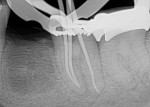

Even a seemingly well-completed root canal treatment (RCT) can fail if all of the pulpal tissue is not fully removed. In this case, the GentleWave® Procedure (Sonendo, Inc., gentlewave.com/doctor) was used to successfully retreat a failing traditional RCT. The GentleWave System is the first and only FDA-cleared system for RCT that addresses the limitations of conventional methods by combining procedure fluid optimization, broad-spectrum acoustic energy, and advanced fluid dynamics to debride and disinfect deep regions of the complex root canal system in a less-invasive procedure that preserves tooth structure. Tooth No. 19 was removed due to a fractured root prior to retreatment of tooth No. 18. The patient was administered anesthetic, and a rubber dam was placed for isolation. A conservative removal of the existing gutta-percha was accomplished using minimal rotary files. A SoundSeal® platform was constructed onto the tooth and treated with a CleanFlow™ procedure instrument (PI). The CleanFlow Technology cleans and disinfects without the PI entering the tooth. After 8 minutes and 15 seconds, the CleanFlow PI was removed and the canals dried. The molar system was filled to complete the retreatment in a single visit. Postoperative 2D and 3D radiographs demonstrated outstanding apical results. At the 1-month follow-up appointment, the patient reported no postoperative pain.